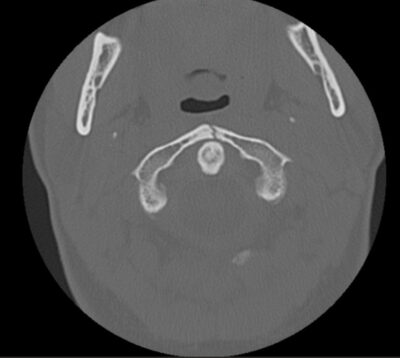

Jefferson fractures refer to a burst fracture of C1 and may involve both the anterior and posterior arches. The mechanism is usually from an axial load (i.e., diving). The fracture is seen on an odontoid view, but this view is difficult to obtain in children < 3 years of age. Typically, there will be a lateral offset of the lateral mass of C1 of > 1 mm from the vertebral body of C2. A pseudo-Jefferson fracture can be seen between 2-6 years of age secondary to the increased growth of the atlas compared to the axis.

Figure: A Patient with a C1 burst fracture